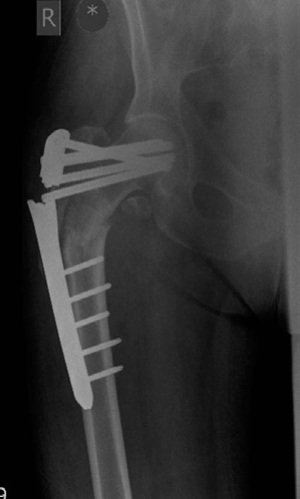

Minute 2 EXAMINER : This woman’s fracture was managed elsewhere and presents during your on-call week with this complication. Can you explain what has happened? (Figures 8.10 and 8.11.) CANDIDATE : This lady was treated with a fixed-angled locking plate. Two things are perhaps responsible for this failure: biomechanics and biology.

Figure 8.10 Anteroposterior (AP) radiograph right femur with fixed locking plate in situ.

Looking at the postoperative radiograph, there is a gap at the fracture site especially medially. The fixed-angled device has been used with locking screws with five screws on either side of the fracture, which will make it a very rigid implant. This will prevent any micro-motion necessary for callus formation. In addition, there is a fracture gap and lack of compression that will preclude primary bone union. This has resulted in a delayed union/atrophic non-union at the fracture site.

The implant has been under constant biomechanical load, which has led to the fatigue failure of the implant. In this particular design there is a stress riser at the junction of the last proximal locking hole and the tapered part of the plate, which dictates the failure point in the implant. In addition, the plating device is applied on the lateral aspect of the femur increasing the lever arm for the moment of force as compared with a cephalomedullary device, which further puts the fixed-angle